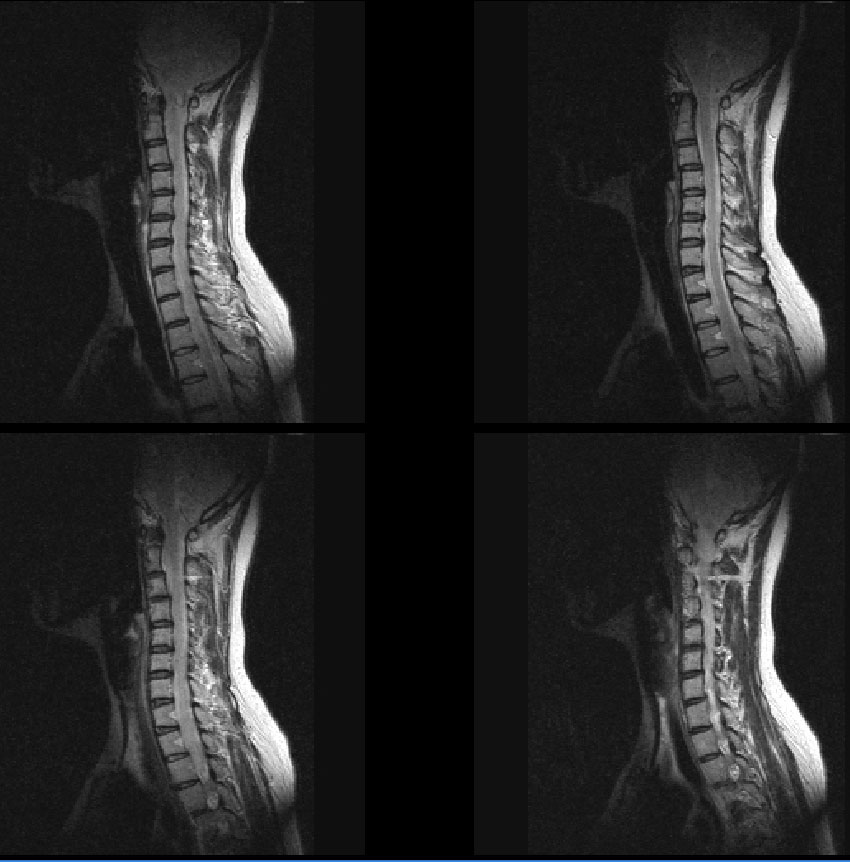

Ž* ֹǰ (ֹȣ : dbd34ccf22cb ) , ü Ư Ű 157 Cm ü 53 Kg 39 ȯ 1C., 1C.̸ , 1C.ٱ Ű ̻, 1C.ٺҸ, 1C.ٸǷ, 1C., 1C.ں, 2C.ھȱ , 2C.ھȱ, 2C.ٴ, 6C.ڸ , 6C. κ Ḳ , 6C.ھ Ḳ , 6C.ڻ , 1T.ڼո , 1T. κ , 1T.꿪 ĵ 3T.ڵ , 2T. Ʒκ 5T.ȯ ҷ, 6T.꿪 ĵ, 3L.ڱñ. 3L.ڽѻ Ǵ Ҽ, 4L.ڵ Ʒ , 5L. , (). , ().ڲ ĿCڸ(ĸ), , Ͽ ũ(߰Ż), հ , ġ, , Ḳ ġ Ǵ , , ȱ ǰϰų Ǵ ġ Ҹ ġ ô ħ Ʈ 氨 ź Ǻ, ȭ ʴ Ǻΰ ͳ ˻ڷ õ 1. c ( 5,6 ־) 2008 1 MRI. 5 ڸ Ǿְ Ÿ Ҷ ġ, ߳ġḦ ҽϴ. Ÿ ո ֽϴ. 2. ô - 13, 10 ߸ S 3. , ĵ, ڱñ, ȯ ȵǴ ̰ , Ǿ ϴ. |